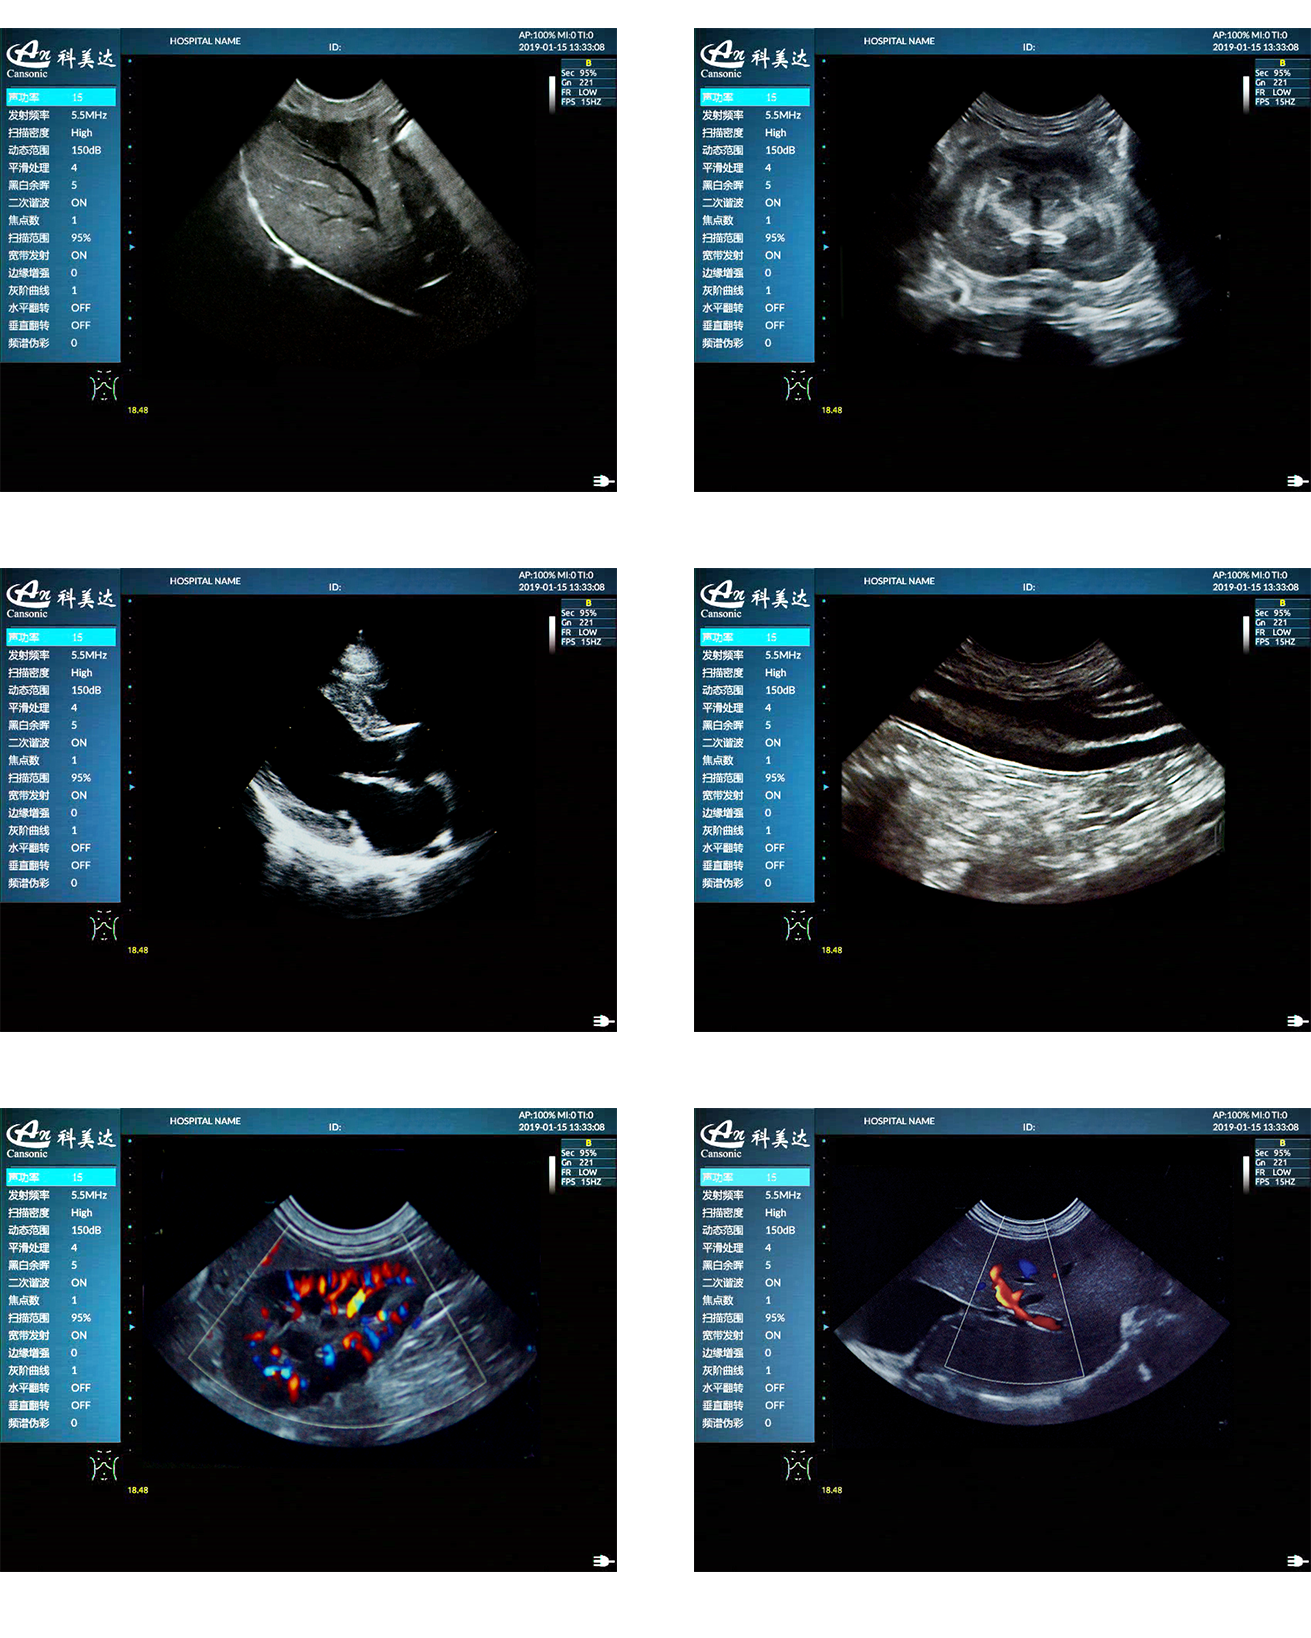

1、超高性價比便攜獸用彩超,以優異的產品性能,提供豐富的動物彩超診療方案

2、適用于狗、貓、馬、牛、羊等多種動物的腹部、生殖、血管小器官,肌骨等檢查模式

3、斑點噪聲抑制抑制噪聲干擾,使動物組織結構對比度強,減少偽像干擾

4、復合成像技術,提高圖像細節分辨率,保證優異的圖像質量

5、能量多普勒POWER成像模式、彩色多普勒Color成像模式等模式適用于應用掃查

臨床圖示